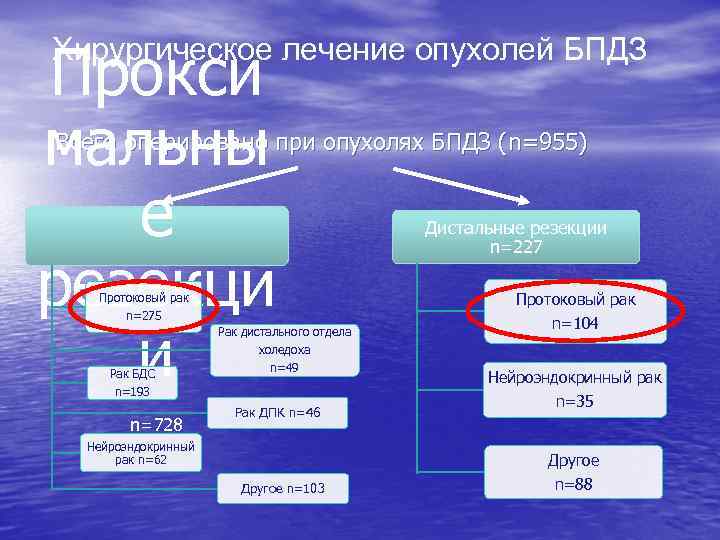

Прокси мальны е резекци и Хирургическое лечение опухолей БПДЗ Всего оперировано при опухолях БПДЗ (n=955) Протоковый рак n=275 Рак БДС n=193 n=728 Рак дистального отдела холедоха n=49 Рак ДПК n=46 Нейроэндокринный рак n=62 Другое n=103 Дистальные резекции n=227 Протоковый рак n=104 Нейроэндокринный рак n=35 Другое n=88